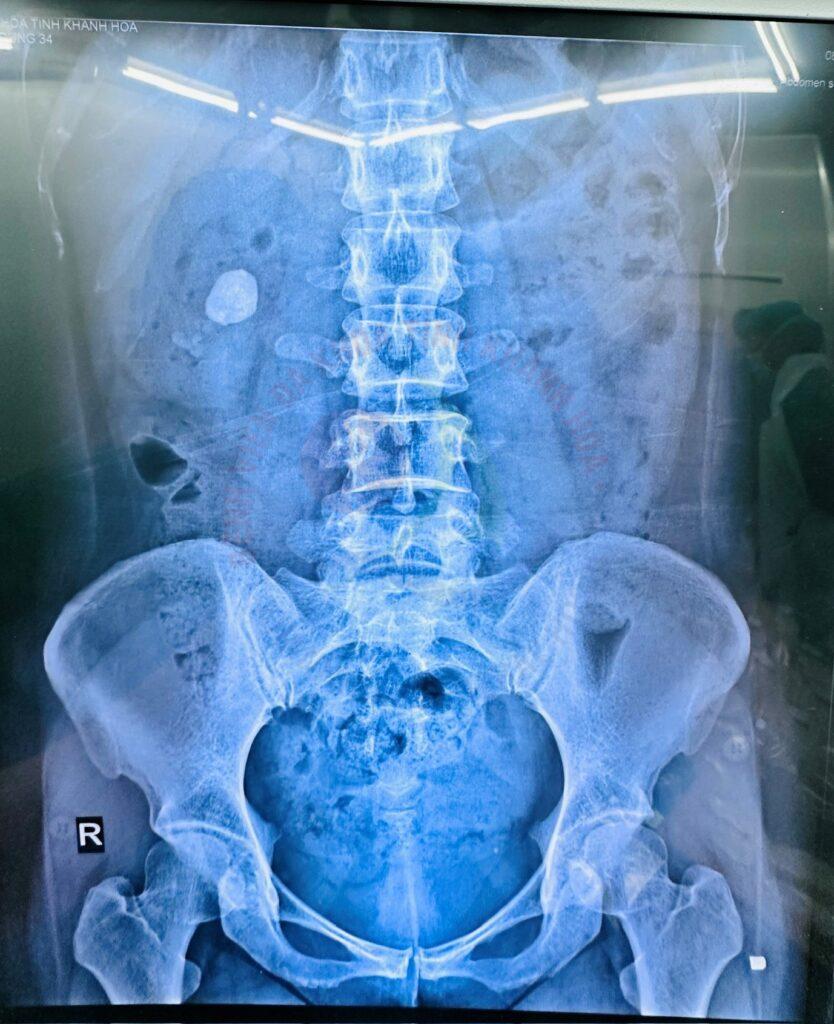

Ông M.X.C (53 tuổi, xã Diên Khánh) nhập viện cấp cứu tại Khoa Ngoại Tiết niệu Bệnh viện Đa khoa Khánh Hòa trong tình trạng đau dữ dội vùng hông lưng. Trên hình ảnh siêu âm và CT, ông được chẩn đoán sỏi thận số lượng nhiều với kích thước khá lớn. Các bác sĩ lựa chọn phương pháp điều trị tán sỏi qua da bằng đường hầm nhỏ, ông nhanh chóng phục hồi và xuất viện sau vài ngày.